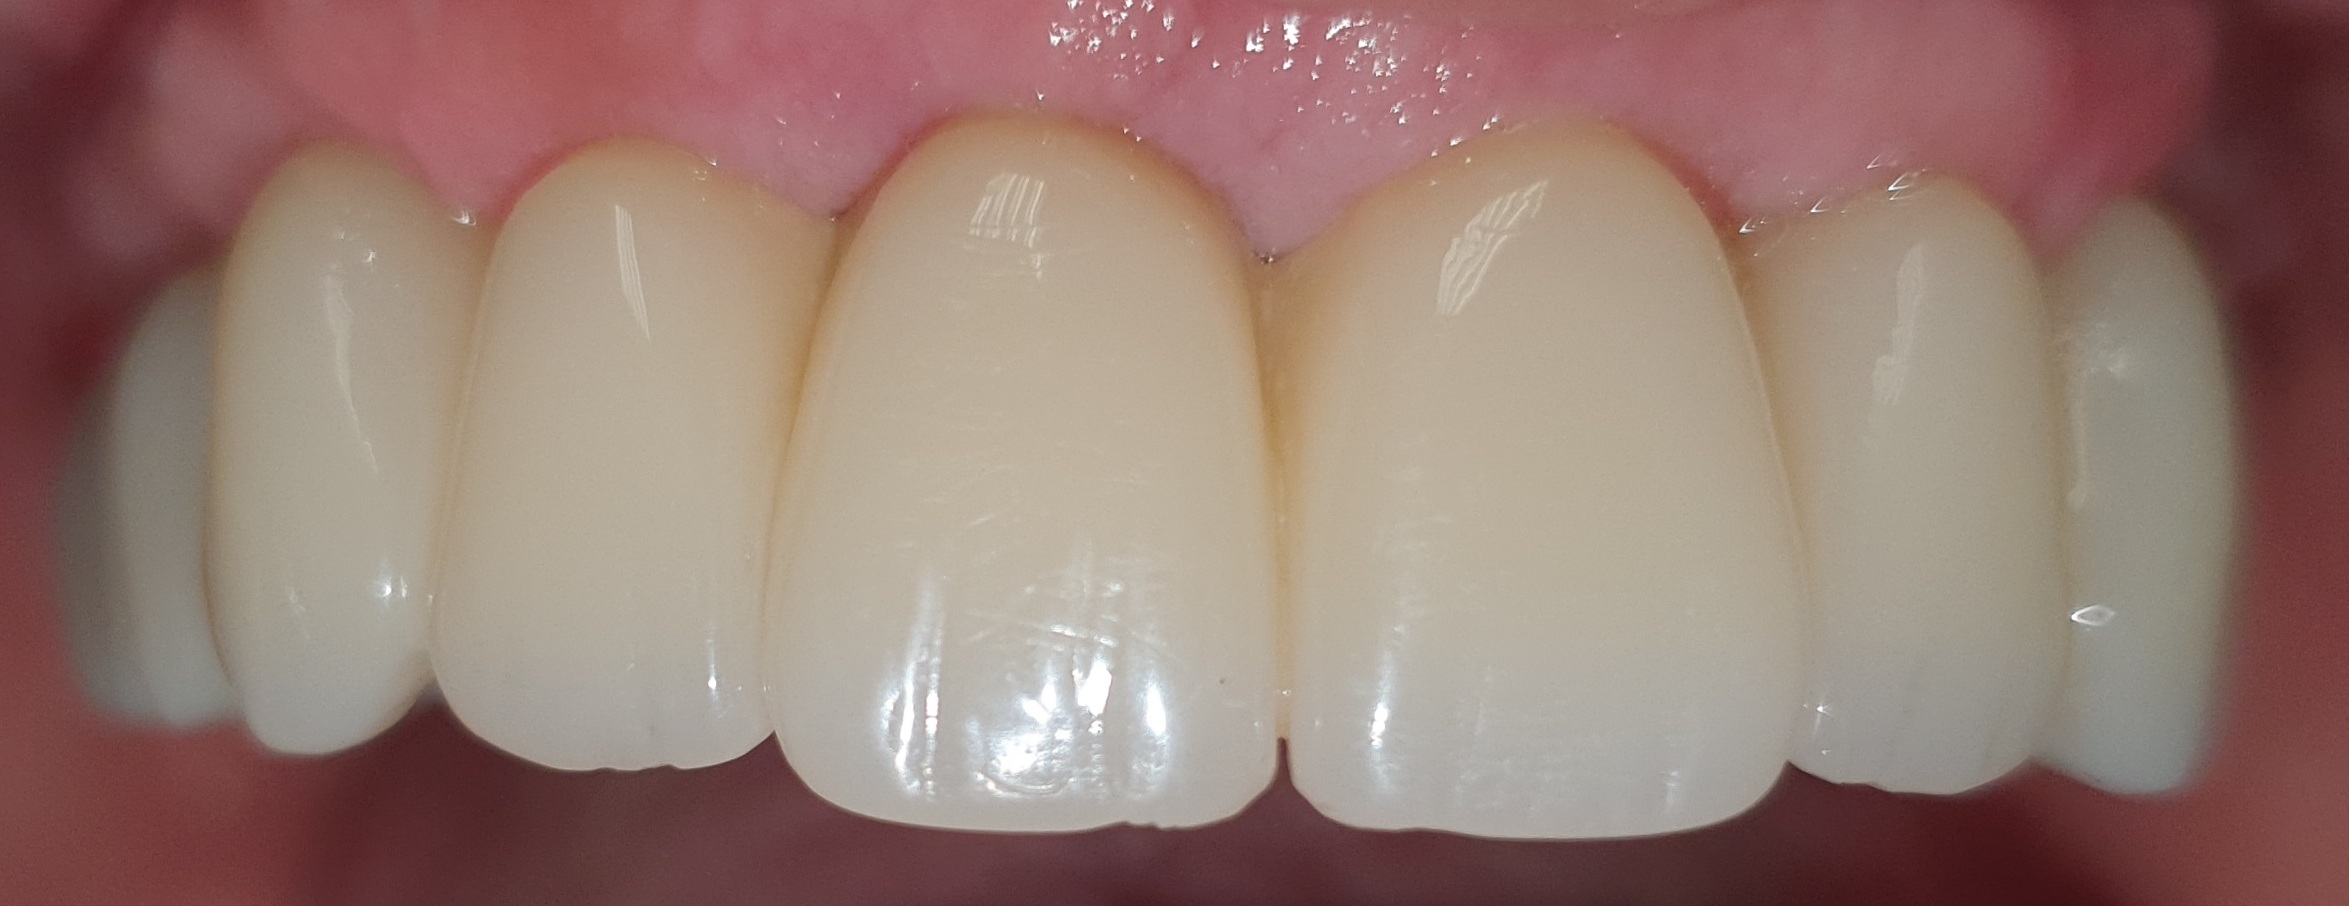

Resa estetica eccellente:

L’utilizzo di software di progettazione permettono di coinvolgere il paziente dall’inizio nelle fasi di progettazione, così da poter scegliere la migliore estetica possibile per riabilitare il suo caso.

Dopo aver stabilito la nuova estetica del paziente, verranno progettati gli impianti e successivamente la dima chirurgica.

Al paziente non rimane che buttare finalmente nel cestino la sua vecchia protesi mobile o il suo vecchio ponte, in quanto questa tecnica ci consente di dimetterlo dallo studio con i suoi nuovi Denti Fissi!